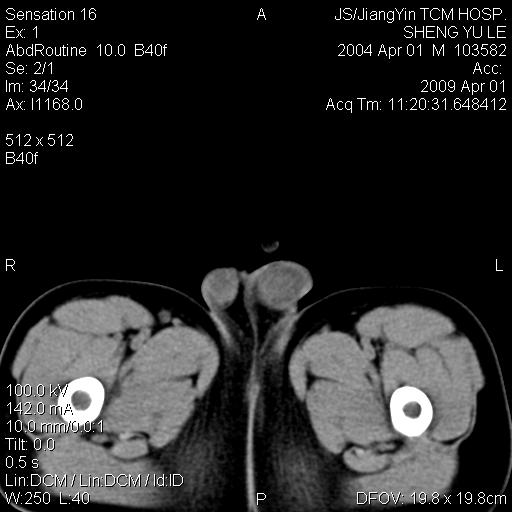

m,5岁。尿痛尿频数天。既往无病史。ct平扫腹盆腔积液。膀胱壁明显增厚。另可见心包增厚。wbc5万,骨髓穿等结果。请指教。

膀胱影像表现结合临床应该是急性膀胱炎症,但为什么有腹水呢?双肾输尿管无扩张,泌尿系压力应该不大不至于引起尿外渗,应该是腹膜感染引起的,但楼主没有提及相关症状,腹膜及膀胱结核?患者白细胞5万(结核不至于这么高啊),脾脏增大,是不是有白血病?进一步检查。。

腹水,膀胱壁增厚,wbc5万,结合临床,支持感染性疾病---感染性腹膜炎、腹水,急性膀胱炎,败血症。期待结果。